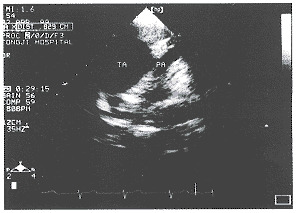

图1 肺动脉起源于动脉干

中国超声医学杂志991235 患儿男性,9岁,生后6月左右出现哭闹后口唇发绀,2岁开始出现蹲踞现象,今来我院就诊以明确诊断。体检:口唇略发绀,杵状指,胸骨左缘三、四肋间闻及Ⅲ~Ⅳ/Ⅵ级收缩期杂音,P2不亢进,胸骨左缘第二肋间闻及粗糙连续性杂音。心电图示:1.窦性心律,2.右室肥大。超声心动图所见:室间隔上部缺损达19mm,并可见一增宽(34mm)的动脉骑跨于室间隔之上,骑跨率约50%,室间隔增厚达9mm,右室壁增厚达7mm,心底短轴切面上未见肺动脉瓣,在主动脉与肺动脉之间有一通道(图1)。彩色多普勒及频谱多普勒显示在该通道处及肺动脉主干内可见五彩镶嵌血流,并测及连续性湍流频谱(图2),另于室缺处见双向分流,收缩期左、右室血流均进入增宽的动脉内。从外周静脉注射声学造影剂后,可见造影剂先出现于右室内,随后出现于左室流出道及主动脉内,然后造影剂经上述通道流入肺动脉。超声心动图诊断:先天性心脏病永存动脉干(Ⅰ型)。